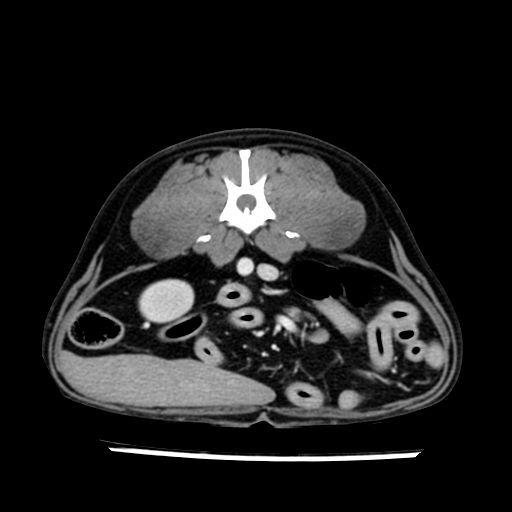

prescritto esame TAC

sequenza immagini limitata al fegato reni e surreni

le immagini ecografiche rispetto alla tac datano circa 7 mesi prima ,le surrenali sono normali nonostante il test acth sia risultato positivo .all’esame TAC dopo diversi mesi risultano aumentate armonicamente nel volume e si individua un forte sospetto di adenoma ipofisario .

sospetto adenoma ipofisario vs. meno probabilmente meningioma della base; intertiziopatia polmonare; lesione espansiva epatica, verosimilmente del lobo laterale sinistro, di sospetta natura neoplastica; lesioni spleniche di natura da definire; iperplasia/ipertrofia delle ghiandole surrenali, bilateralmente; vertebra di transizione del rachide toracico; tenosinovite cronica del muscolo bicipite brachiale di destra.